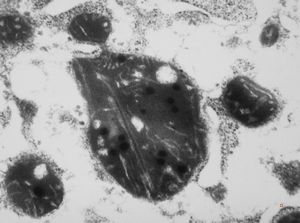

F,45y. | metastasis - carcinoid